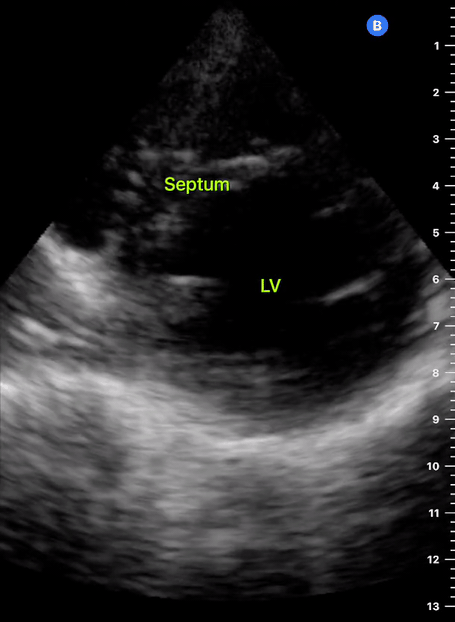

A correct PLAX view will align with the heart’s long axis, producing a sagittal cut. On the screen, from the top, we see the right ventricle, the interventricular septum, the left ventricle with its outflow tract, the aortic valve and aortic root, and the left atrium. It is essential to look for the descending aorta, which appears in a transversal cut deeper to the LV.